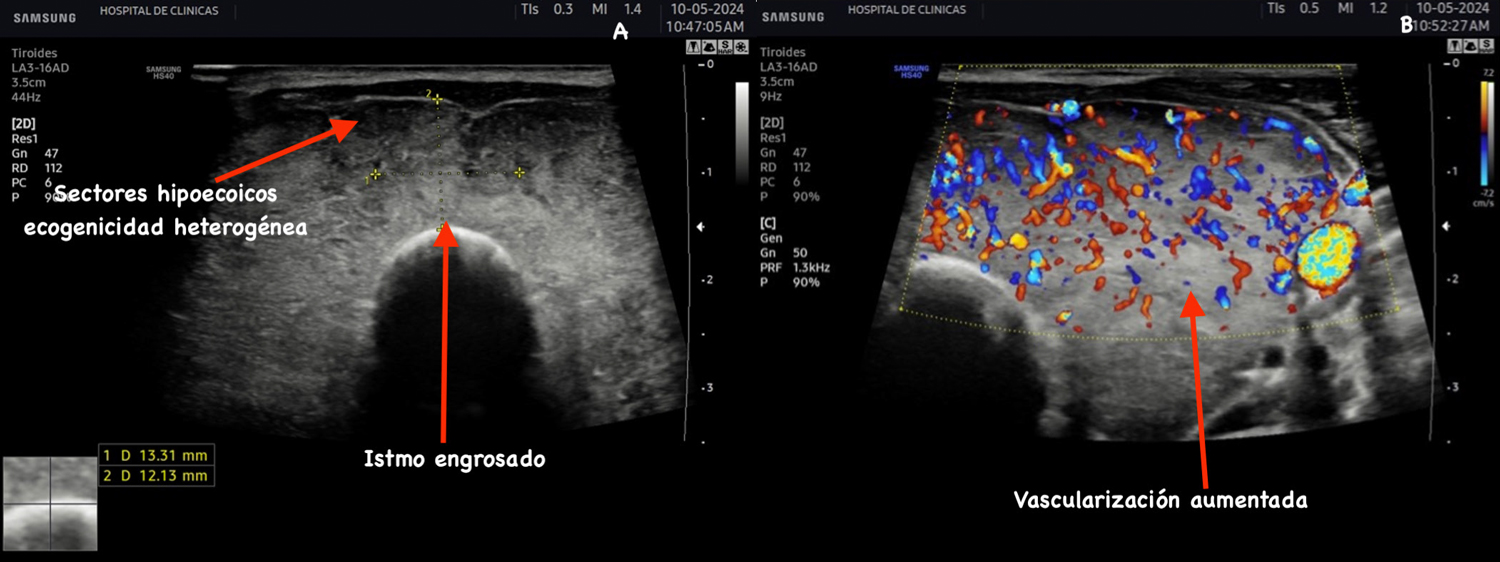

Protrusión de las superficies anteriores de los lóbulos,

agrandamiento del istmo, redondeo del contorno angular

normal. Disminución difusa de la ecogenicidad. Aumento

de la vascularización significativa del parénquima de

forma simétrica (Figura 5)7.

La hipoecogenicidad observada en la enfermedad de Graves se debe a la hipertrofia e hiperplasia de la células foliculares e infiltrado linfocitario, disminución del contenido de coloide en los folículos y aumento de la vascularización como se observa en la figura 56.

Figura 5: Corte transversal y longitudinal de tiroides de paciente con EGB. Se señala el itsmo engrosado, disminución de la ecogenicidad, estructura

heterogénea, aumento de la vascularización del parénquima.